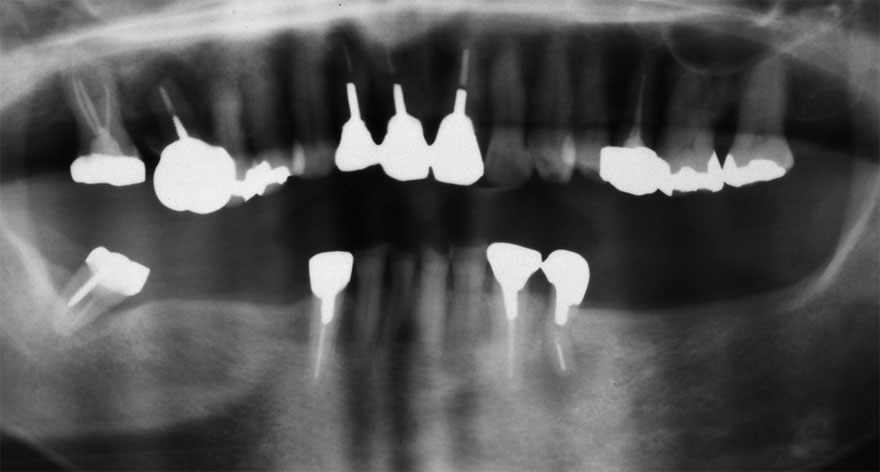

初診時 36歳 女性 平均歯槽骨喪失量:2.70mm

30年後 66歳

平均歯槽骨喪失量:3.26mm

30年間喪失量:-0.55mm

年間喪失速度:-0.018mm

(ケア頻度:3.01ヵ月ごと)